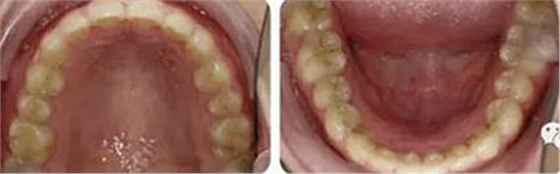

上下牙列輕度擁擠,牙弓偏尖圓形;前牙深覆合深覆蓋;雙側(cè)磨牙尖牙偏遠(yuǎn)中關(guān)系。

治療23個(gè)月結(jié)束??梢?jiàn)兩側(cè)尖磨牙達(dá)到中性關(guān)系,上下牙列排齊整平,前牙覆合覆蓋正常,中線(xiàn)齊。

曲斷可見(jiàn)牙根基本平行。